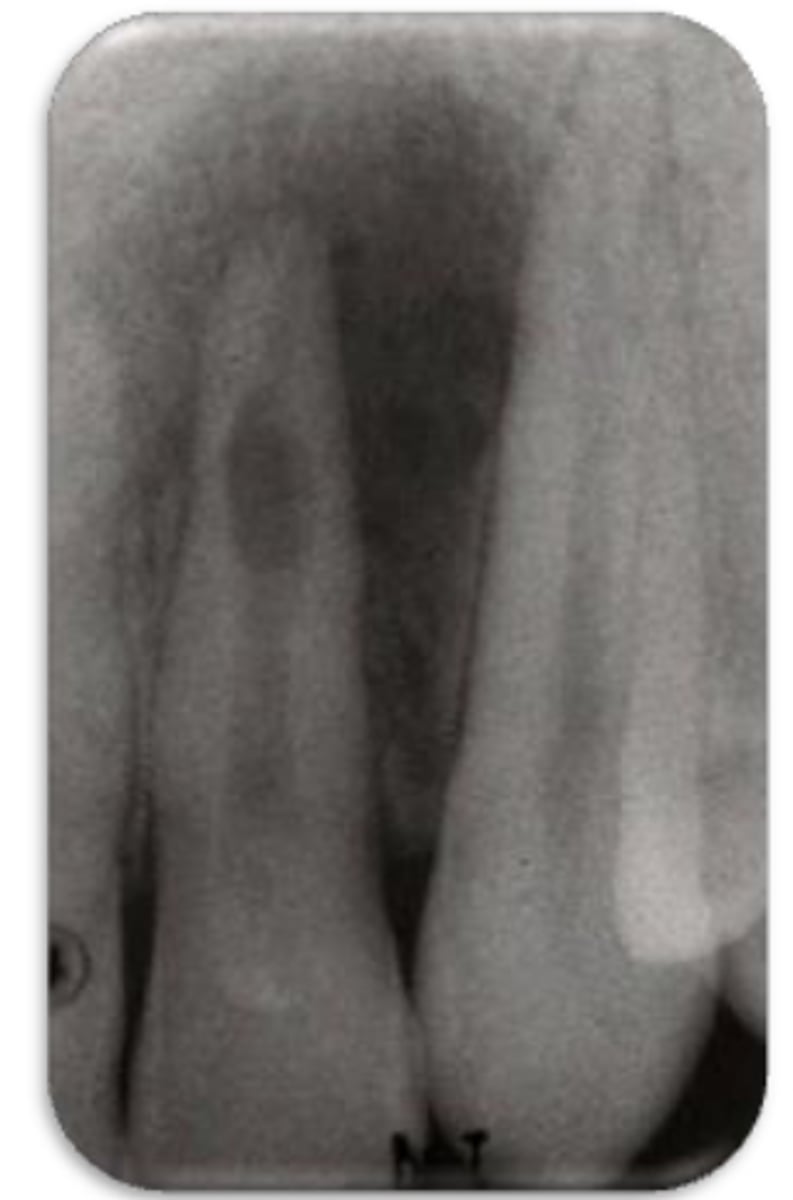

ID the problem:

- Ballooning out of root canal

internal resorption

How can you confirm if a root has internal resorption?

Take a few different angles